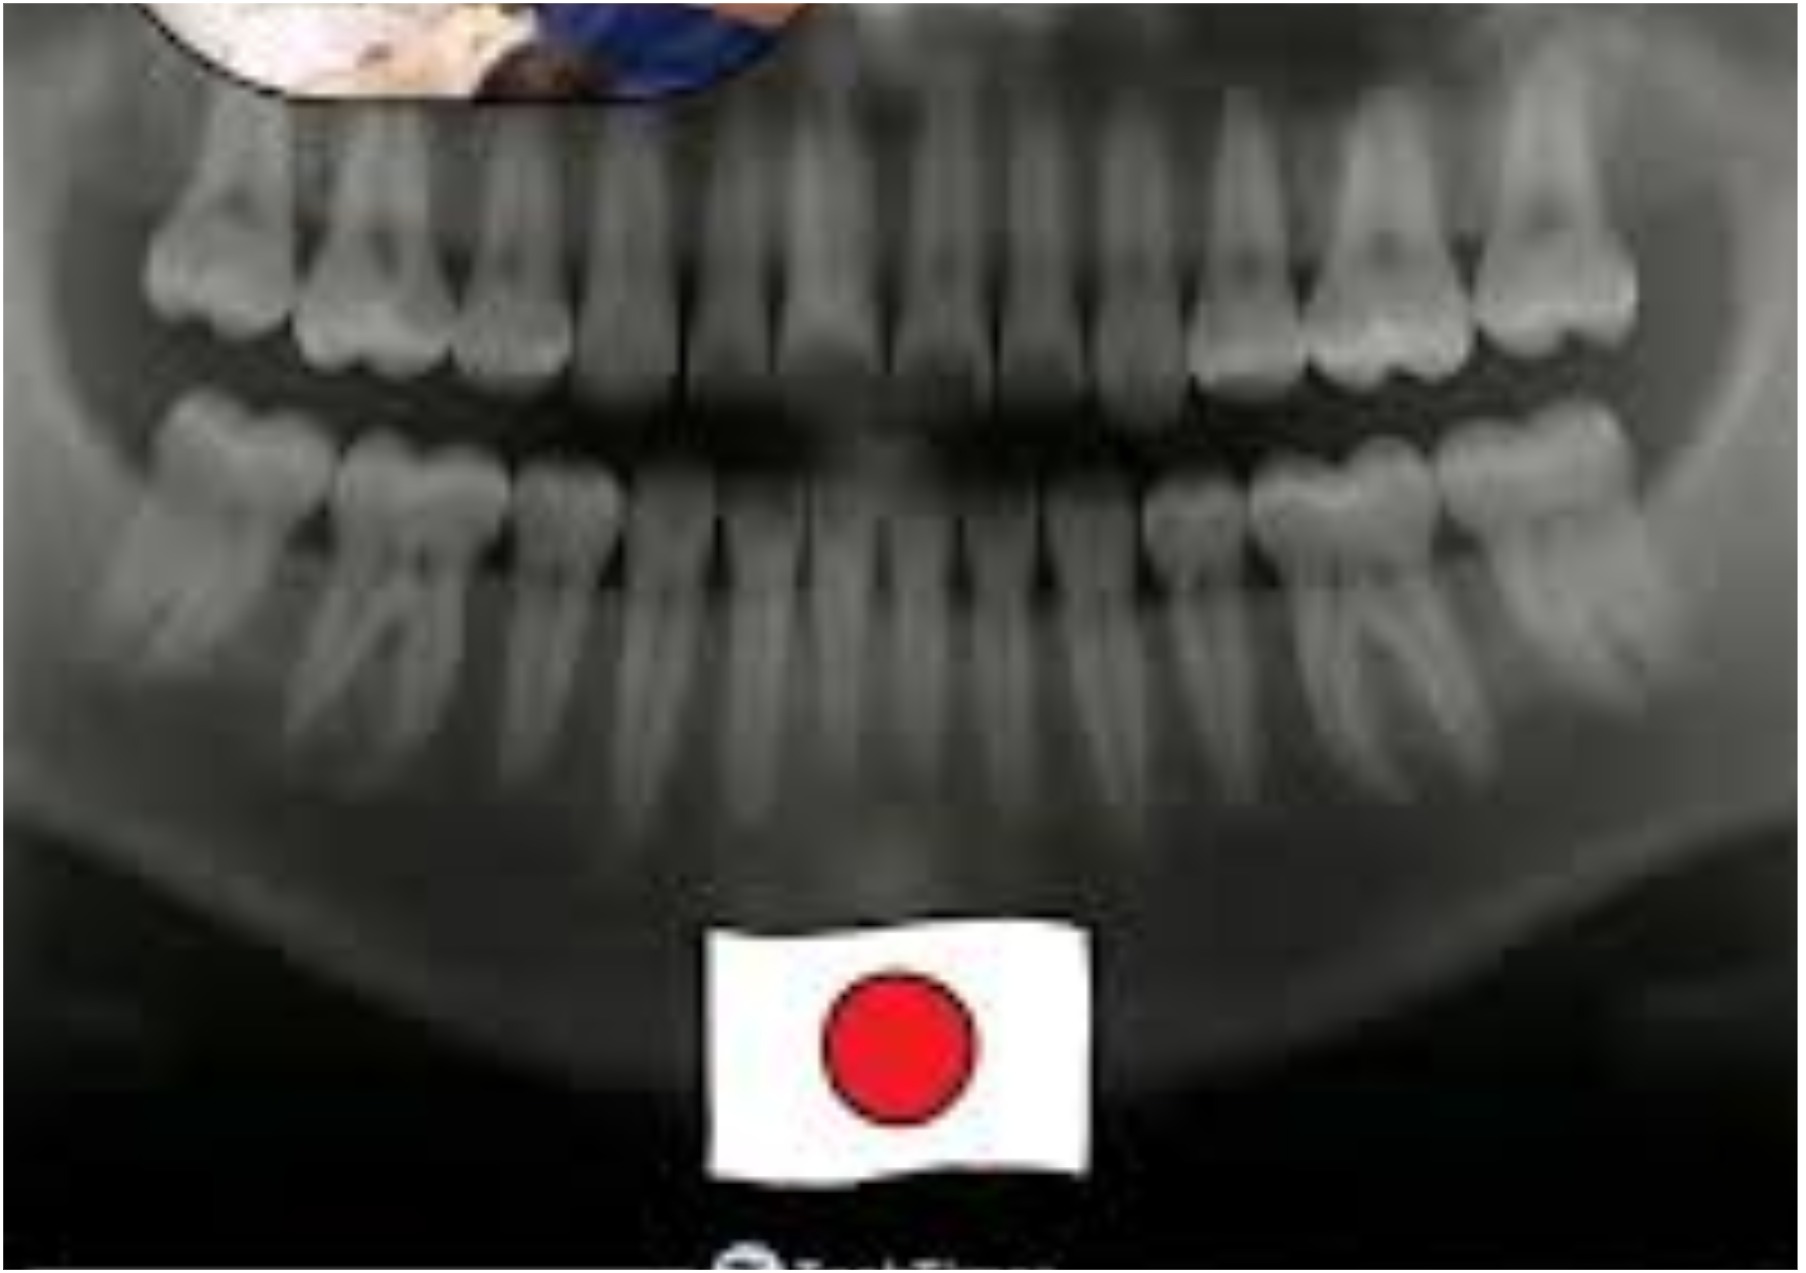

Япон окумуштуулары стоматология тармагын түп-тамырынан өзгөртүшү мүмкүн — алар адамга табигый жол менен жоголгон тиштерин кайрадан өстүрүүгө мүмкүнчүлүк берген дарыны иштеп чыгышууда.

Китано госпиталындагы Медициналык изилдөө институтунун доктор Кацу Такахашинин жетекчилиги астында жүргүзүлүп жаткан бул дарылоо адатта жаңы тиштердин калыптанышына тоскоол болгон USAG-1 белогун бөгөттөө аркылуу иштейт. Чычкандарда жүргүзүлгөн тажрыйбаларда бул белоктун иши токтотулганда «үчүнчү түйүндөр» жанданып, жаңы тиштердин өсүшүнө алып келген.

Изилдөөчүлөр акулалар жана пилдер сыяктуу табигый түрдө бир нече муундагы тиштерди кайра өстүрө алган жаныбарлардан шыктануу менен, адамдарга клиникалык сыноолорду баштоону жана 2030-жылга чейин бул дарыны рынокко чыгарууну пландап жатышат.

Бул дары улгайгандыктан, жаракаттан же генетикалык себептерден улам жоголгон тиштерди кайра өстүрүүгө жардам берип, имплант менен протездерге радикалдуу альтернатива сунуштайт. Муну менен ондогон жылдар бою жүргүзүлгөн регенерация боюнча изилдөөлөрдү практикалык, ишке аша турган жаңылыкка айлантат.